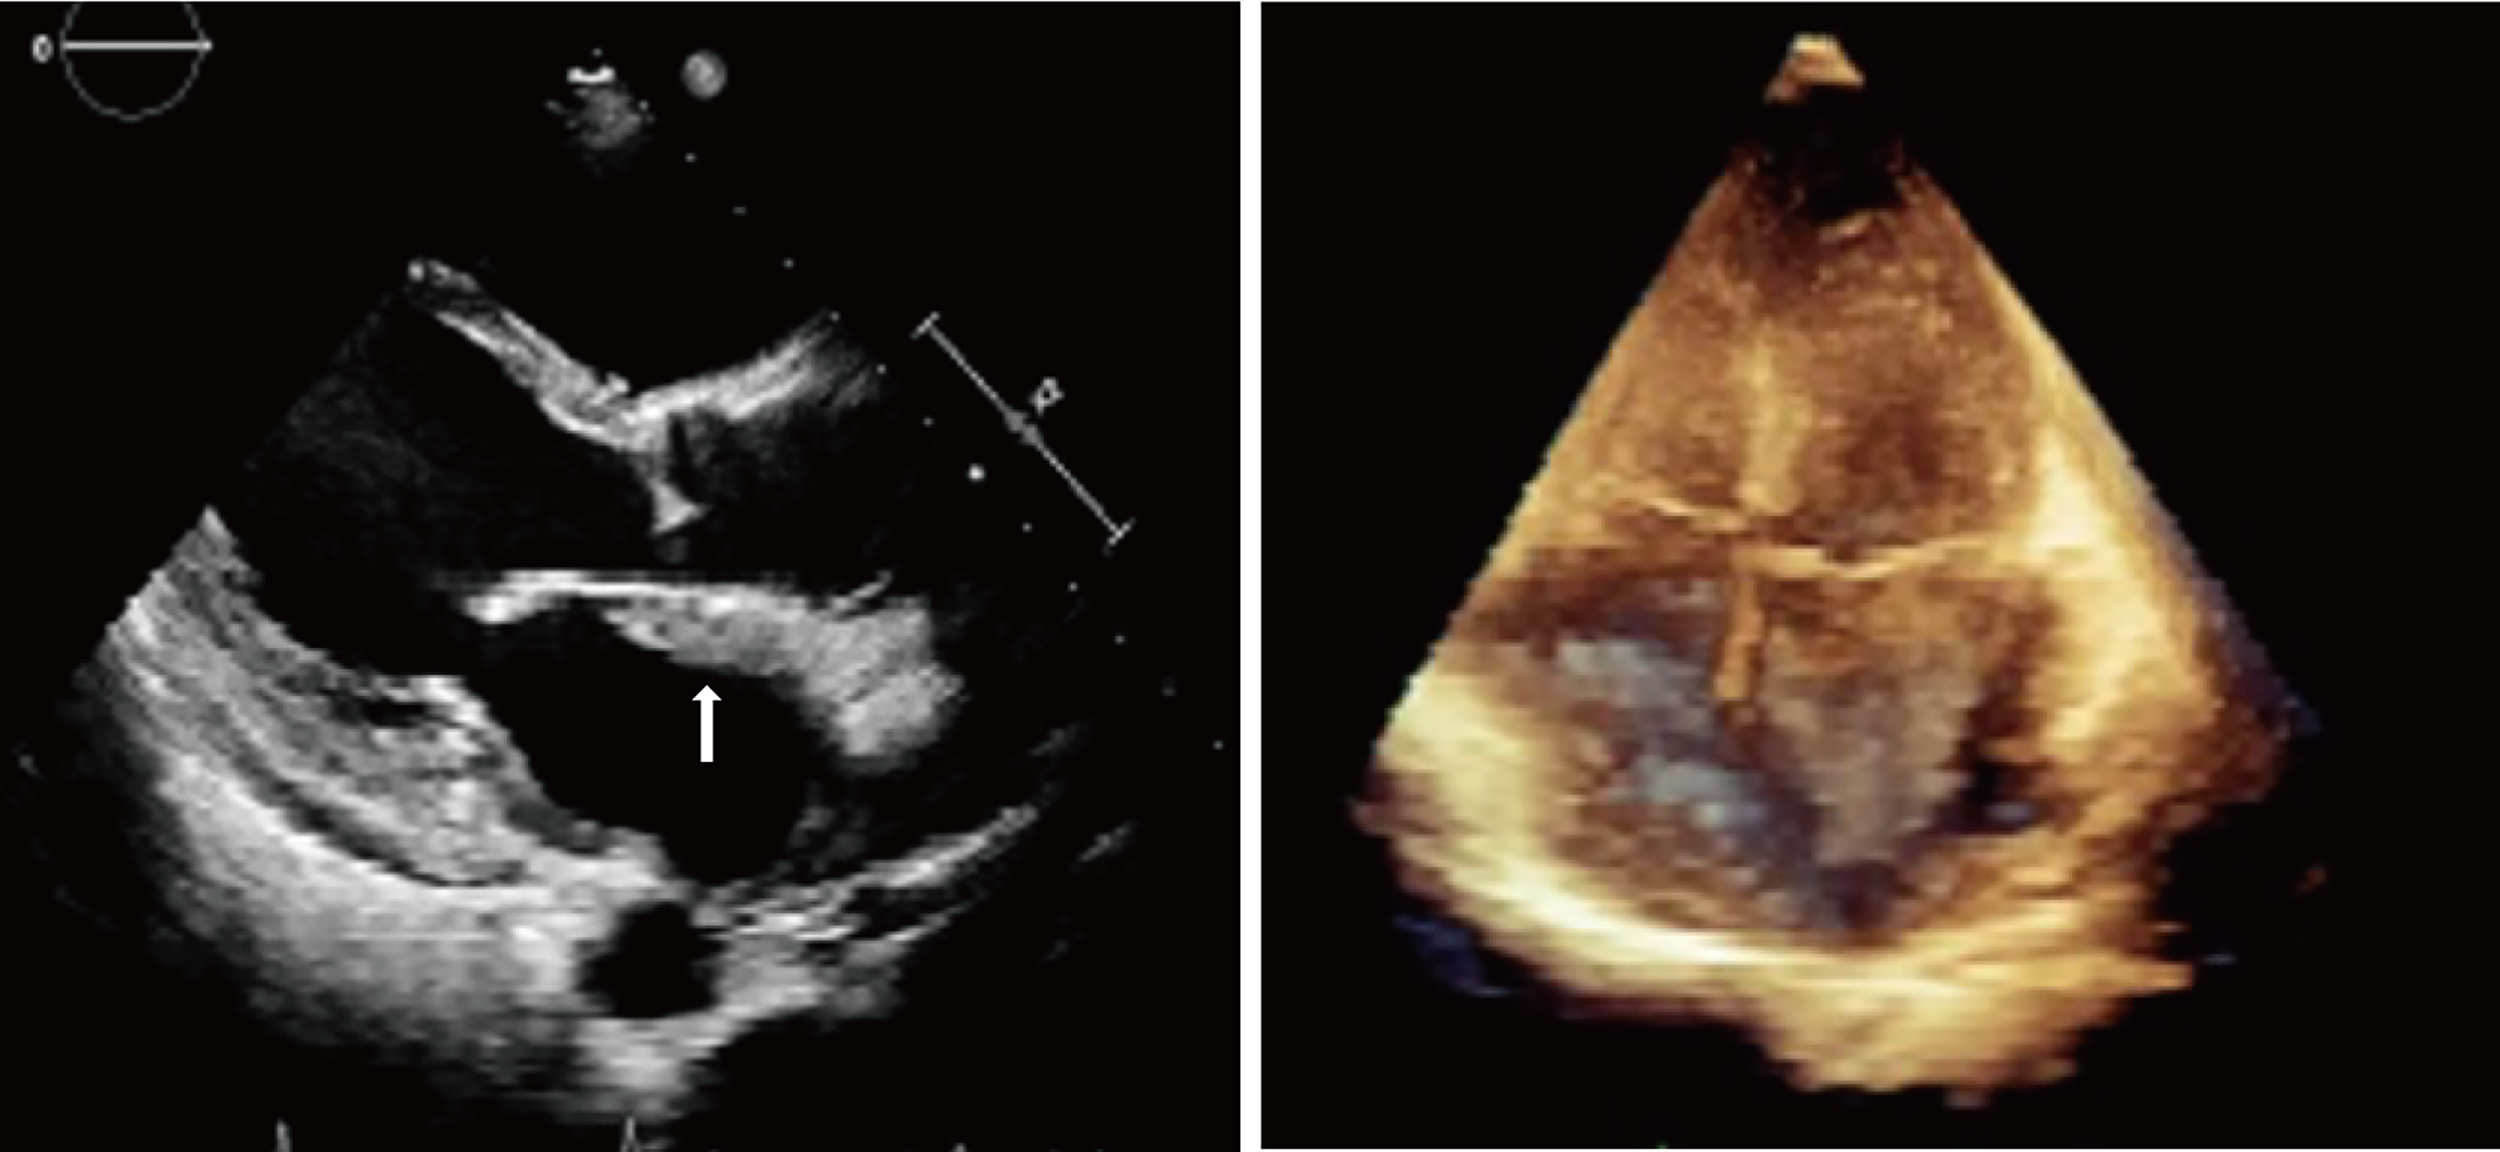

The initial electrocardiogram (ECG) showed a complete atrioventricular block (AVB) with a junctional rhythm (Figure 1A). Blood examination showed troponin levels within normal range and the brain natriuretic peptide precursor level was 1388 pg/ml. Transthoracic echocardiography (Figure 2) shows a homogeneous isoechoic layer thickening of the endocardial surface of the left atrium across the entire left atrial wall with a thickness of approximately 1.06 cm, and the same changes were observed in the left auricle. The rest of the structures were indistinguishable. Left cardiac ultrasonography suggested a homogeneous isoechoic filling of the left atrial wall and left auricle with no perfusion in the imaging.

Figure 2 Transthoracic echocardiography showed a homogeneous isoechoic layer thickening of the endocardial surface of the left atrium across the entire left atrial wall.